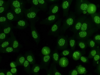

Vad kallas detta mönster och när kan det ses?

Homogen ANA

- SLE